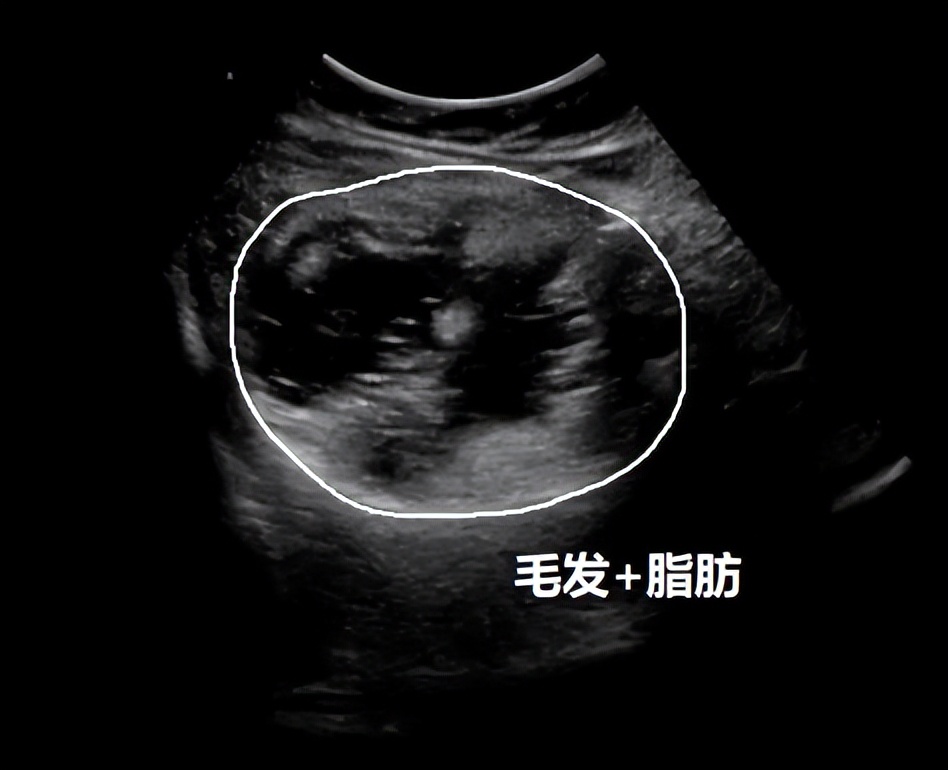

03、 卵巢畸胎瘤

这是一种病理性囊肿,好在一般是良性的。卵巢畸胎瘤由胚胎来源的细胞形成,可包含人体的各种成分,如头发、骨成分或脂质。

卵巢畸胎瘤的病因和发病机制至今不明,并且往往没有明显的临床症状。95%以上为良性的成熟性畸胎瘤,超声图像具有特征性,诊断比较明确,以手术切除为主。